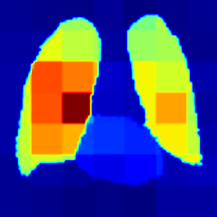

Thoracic disease detection from chest radiographs using deep learning methods has been an active area of research in the last decade. Most previous methods attempt to focus on the diseased organs of the image by identifying spatial regions responsible for significant contributions to the model's prediction. In contrast, expert radiologists first locate the prominent anatomical structures before determining if those regions are anomalous. Therefore, integrating anatomical knowledge within deep learning models could bring substantial improvement in automatic disease classification. This work proposes an anatomy-aware attention-based architecture named Anatomy X-Net, that prioritizes the spatial features guided by the pre-identified anatomy regions. We leverage a semi-supervised learning method using the JSRT dataset containing organ-level annotation to obtain the anatomical segmentation masks (for lungs and heart) for the NIH and CheXpert datasets. The proposed Anatomy X-Net uses the pre-trained DenseNet-121 as the backbone network with two corresponding structured modules, the Anatomy Aware Attention (AAA) and Probabilistic Weighted Average Pooling (PWAP), in a cohesive framework for anatomical attention learning. Our proposed method sets new state-of-the-art performance on the official NIH test set with an AUC score of 0.8439, proving the efficacy of utilizing the anatomy segmentation knowledge to improve the thoracic disease classification. Furthermore, the Anatomy X-Net yields an averaged AUC of 0.9020 on the Stanford CheXpert dataset, improving on existing methods that demonstrate the generalizability of the proposed framework.